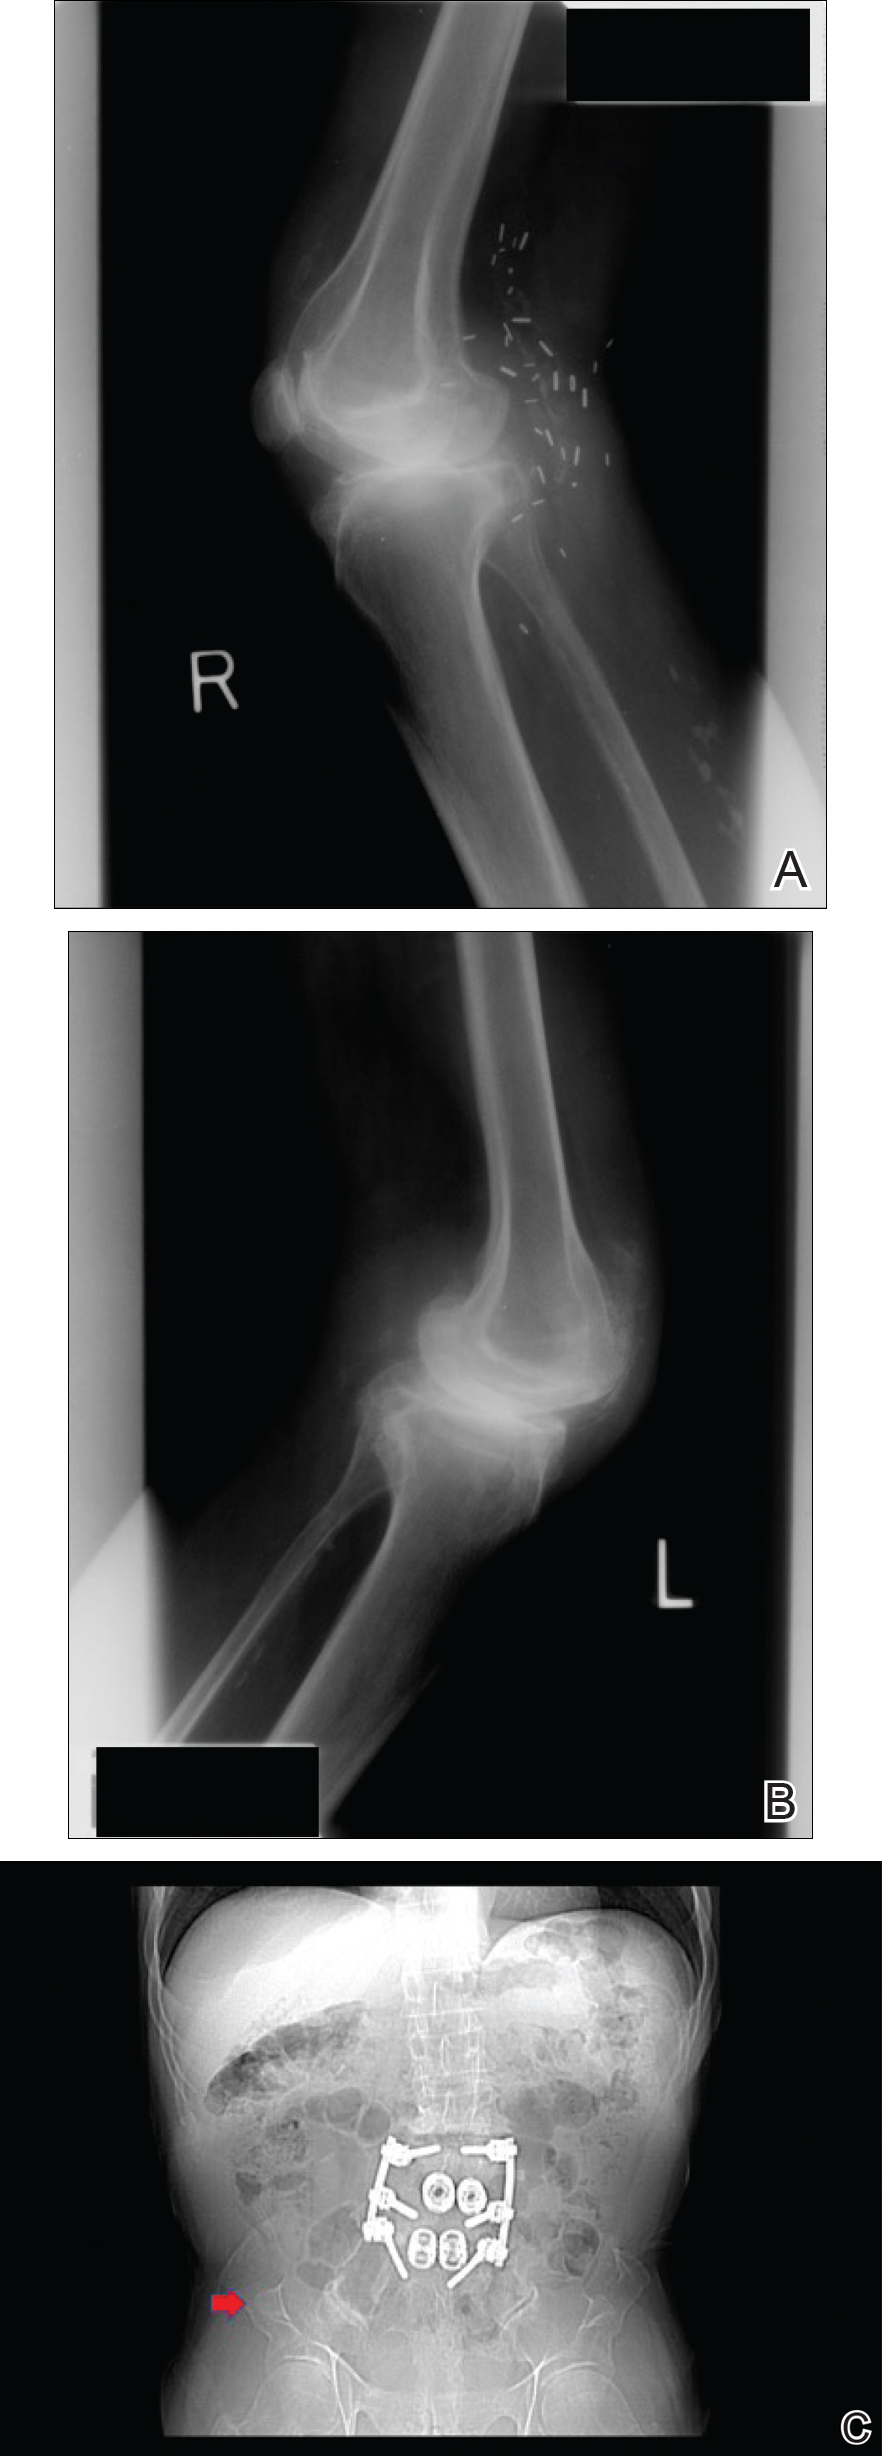

Figure 2. Lateral radiographs of the knee joints demonstrated right patellar hypoplasia (A) and left patellar absence (B). A radiograph of the pelvis revealed bilateral triangular osseous excrescences from the posterior ilia, known as iliac horns (arrow)(C). Metallic orthopedic hardware from multiple spinal surgeries performed on the patient also can be appreciated, presumably long-term sequelae of the patient’s condition.

Physical examination was remarkable for bilateral fingernail hypoplasia that was most prominent on the thumb, with improvement in each nail on progression toward the fifth digit (Figure 1A). Triangular fingernail lunulae, longitudinal ridging, and nail splitting were present (Figure 1A and 1B). Hypoplastic crumbly toenails also were appreciated (Figure 1C). Skin creases over the distal interphalangeal joints of the fingers and toes were conspicuously absent. Limited range of motion was noted in multiple joints, with profound limitation of bilateral elbow extension. Review of prior imaging reports revealed bilateral iliac horns as well as left patellar absence and right patellar hypoplasia (Figure 2). Urinalysis was remarkable for proteinuria and microscopic hematuria. Given the constellation of examination findings and positive family history, a diagnosis of NPS was made.